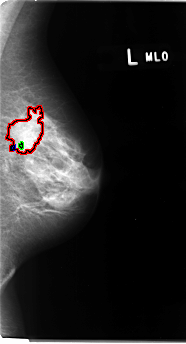

B_3076_1.LEFT_MLO

LEFT_MLO LINES 4816 PIXELS_PER_LINE 2600 BITS_PER_PIXEL 12 RESOLUTION 50 OVERLAY

FILE: B_3076_1.LEFT_MLO.OVERLAY

TOTAL_ABNORMALITIES 3

ABNORMALITY 1

LESION_TYPE MASS SHAPE IRREGULAR-ARCHITECTURAL_DISTORTION MARGINS OBSCURED-SPICULATED

ASSESSMENT 4

SUBTLETY 4

PATHOLOGY MALIGNANT

TOTAL_OUTLINES 1

ABNORMALITY 2

LESION_TYPE CALCIFICATION TYPE AMORPHOUS-ROUND_AND_REGULAR DISTRIBUTION CLUSTERED

ABNORMALITY 3